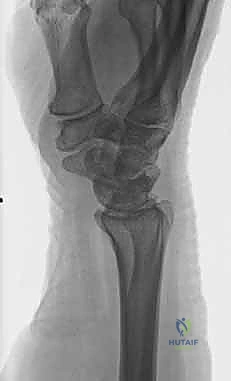

1. الأشعة السينية (X-rays): بوضعيات متعددة (أمامية خلفية، وجانبية دقيقة). الوضعية الجانبية الحقيقية (True Lateral) حاسمة لاكتشاف أي خلع جزئي في المفصل (DRUJ).

2. الأشعة المقطعية ثلاثية الأبعاد (3D CT Scan): تُستخدم في الكسور المفتتة أو كسور رأس الزند المفصلية المعقدة، حيث تعطي خريطة دقيقة للجراح قبل الدخول لغرفة العمليات.